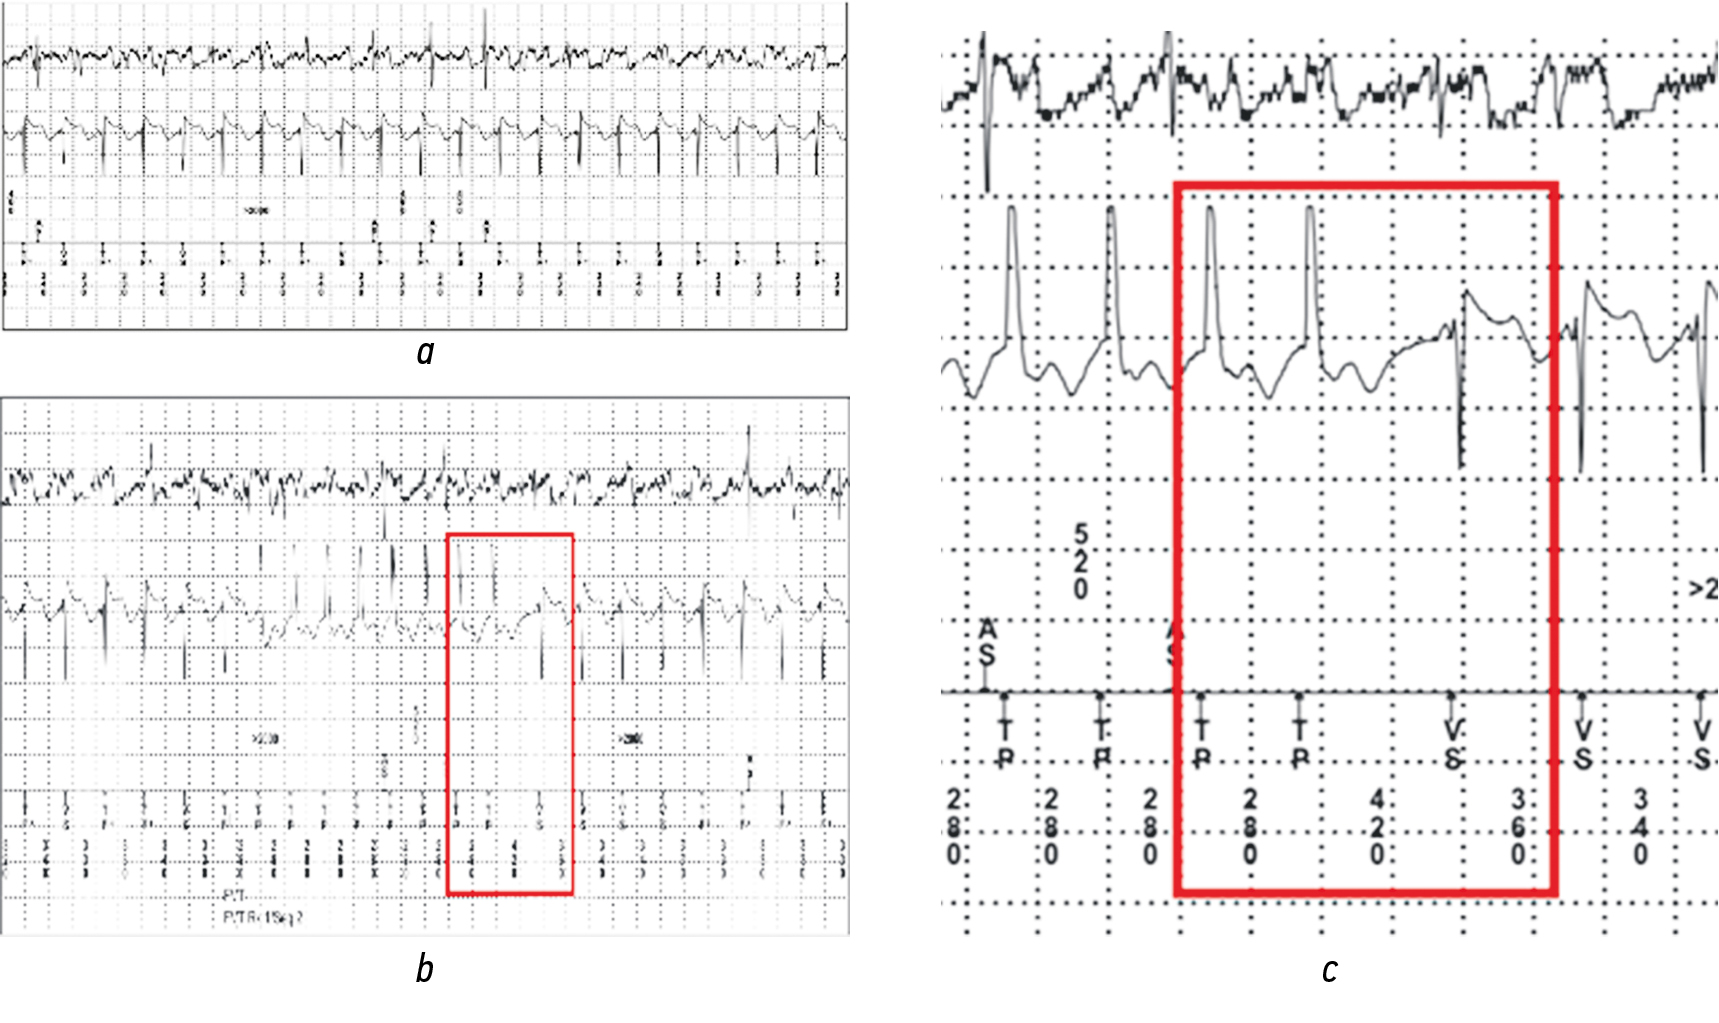

The presence of SM-VT of multiple morphologies increases the potential risk of recurrent VT after successful ablation compared with VT of a single morphology. Therefore, immediately before performing ablation during intracardiac EEPS, the efficiency of future antitachycardiac ATP protocols was tested in the X-ray operating room with stimulation from a quadripolar catheter placed in the area of the defibrillating ICD electrode. This aimed to establish the cause of the inefficiency of the previously used ATP therapy of ICD (before ablation) and test alternative ATP protocols (for customized ICD programming after ablation).

As a result of ATP simulation of ICD protocols in an X-ray operating room, typical ATP therapy using a series of burst stimulations, according to the recommendations of the 2019 Consensus, was deemed ineffective (Fig. 5).

Fig. 4. SM-VT induced during EEPS of two main morphologies

Fig. 5. a — Typical burst pacing from the right ventricular (RV) lead (88% of the SM-VT cycle). After ATP termination, VT continues with the same cycle of 365 ms. b — Typical burst pacing from the RV lead (83% of the SM-VT cycle). VT changed slightly the morphology and continues with the same cycle of 365 ms. c — “Aggressive” antitachycardic burst pacing from the RV lead (approximately 55% of the SM-VT cycle of 200 ms) with no effect. VT was maintained with the same cycle. d — “Aggressive” antitachycardiac burst pacing from the RV lead with a very short interval on the verge of an effective ventricular refractory period (approximately 52% of the SM-VT cycle of 190 ms). At the end of ATP stimulation, VT accelerates to 280–290 bpm and transforms into polymorphic VT (short fragment), with spontaneous arrest

The analysis of the results of intraoperative ATP with ultra-frequent stimulation demonstrated the following:

- The ERP of the ventricles in sinus rhythm was 210 ms.

- The ERP of the ventricles against long-term VT was < 190 ms.

- The ERP of the ventricles with long-term VT was much shorter than the cycle of previously established antitachycardic ICD pacing in episodes of ineffective ATP at the outpatient stage (shortest pacing interval of 270 ms).

This fact was probably the reason for the inefficiency of ATP in this patient at the outpatient stage, which required changing the ATP settings for ICD therapy, which differ from those recommended by the 2019 Consensus.